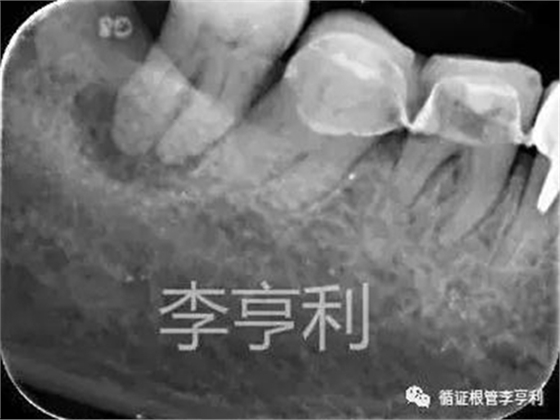

術(shù)前片 (2017-05-16)

輔助檢查:遠(yuǎn)中角度投射根尖片,見(jiàn)斷械影像移向近中,故判斷器械分離于近中頰根,根尖周未見(jiàn)明顯異常 。

遠(yuǎn)中角度投射,紅色箭頭為分離器械 (2017-05-16)

術(shù)前診斷:46根管已開(kāi)始治療,根尖周正常組織,伴發(fā)器械分離 (previously initiated treated with normal apical tissues, complicated by separated instrument)。